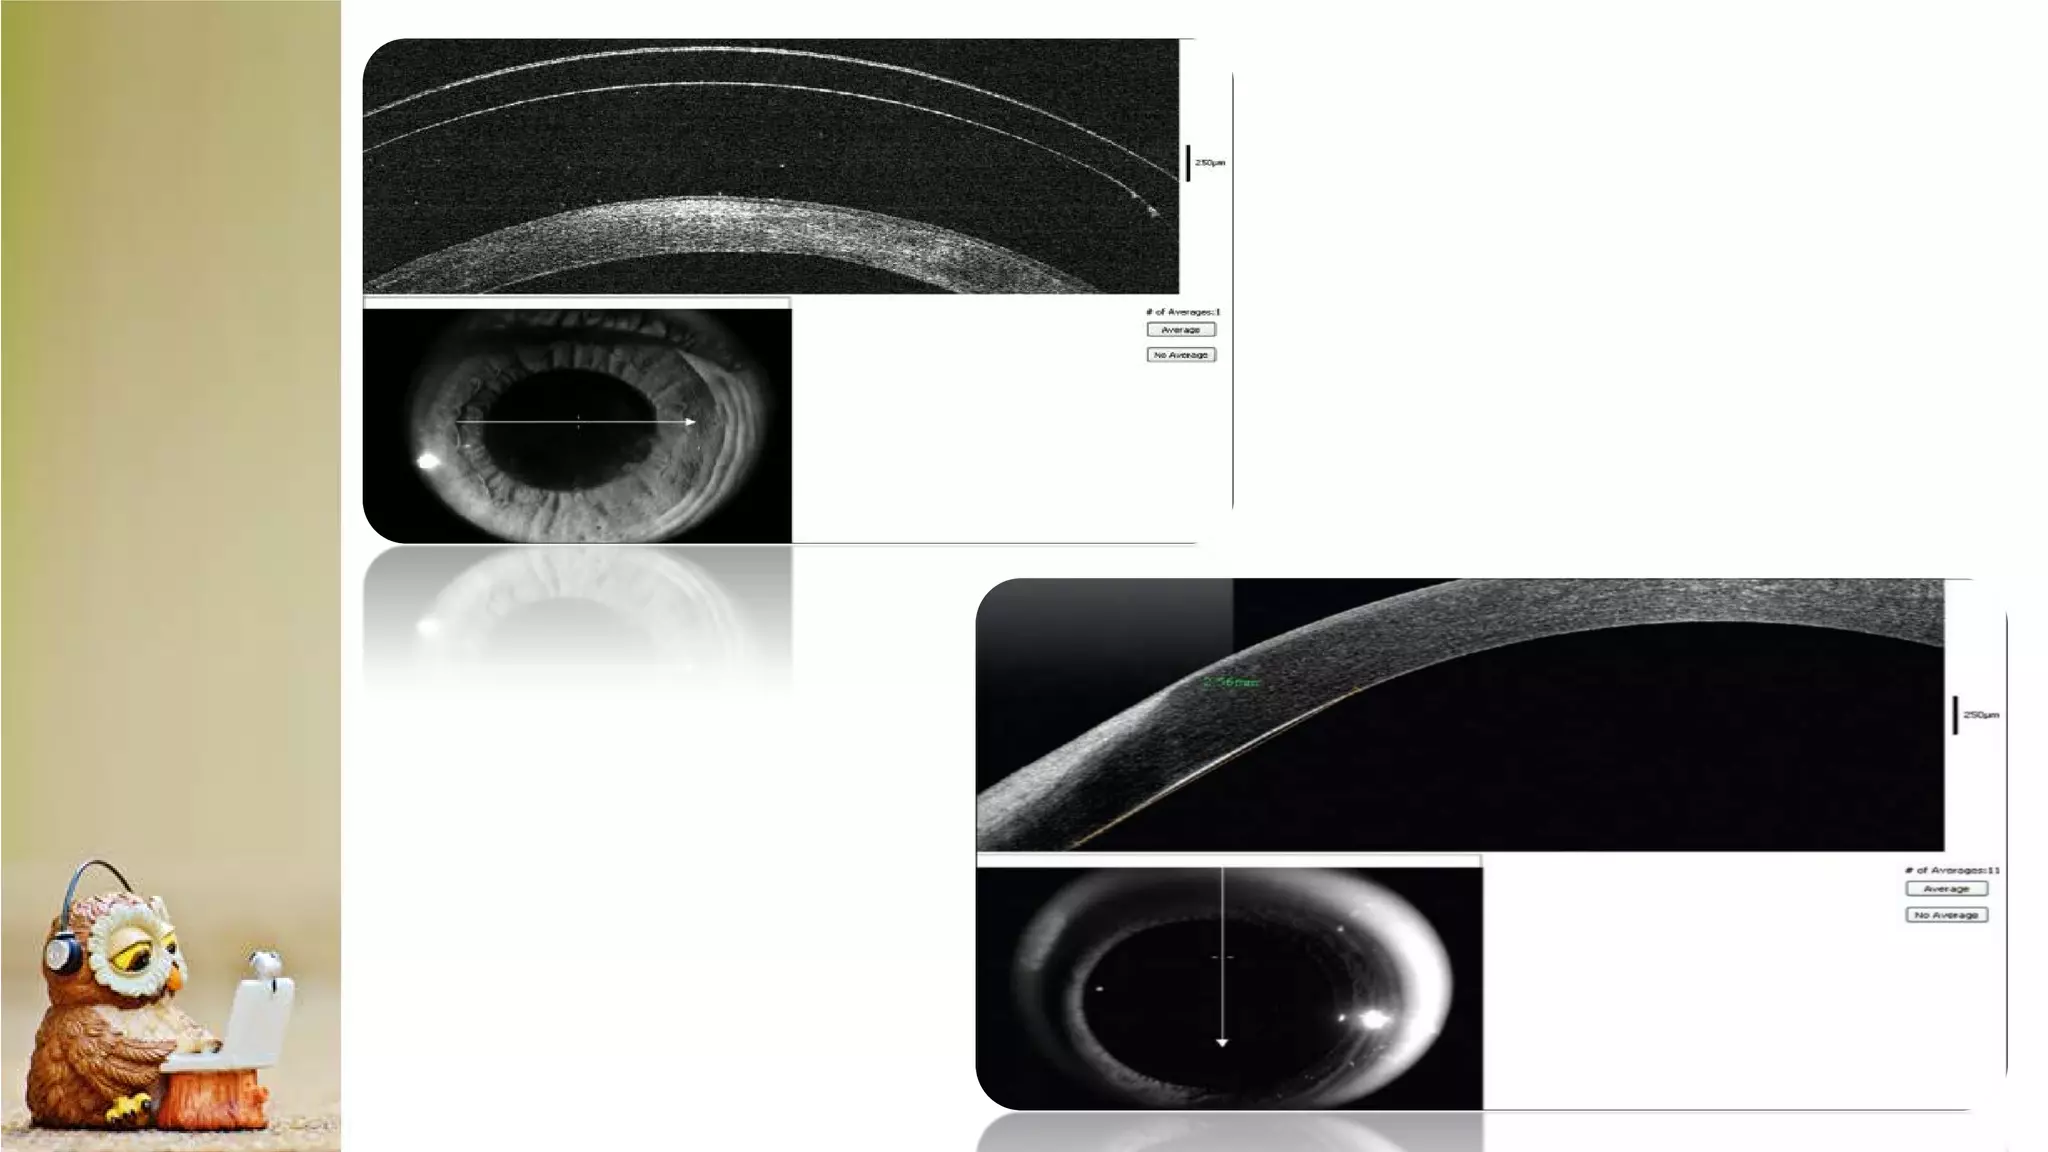

The document discusses Anterior Segment Optical Coherence Tomography (AS-OCT) as a noninvasive diagnostic tool providing high-resolution cross-sectional images of the ocular surface and anterior segment. It details various OCT devices, their manufacturers, measurement types, and scanning speeds, highlighting qualitative and quantitative assessment capabilities. The document also notes limitations such as resolution modes and specific ocular conditions that may affect results.